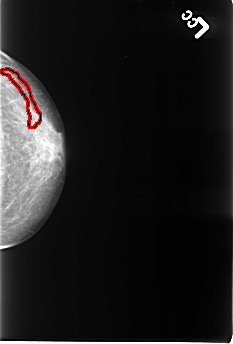

B_3246_1.LEFT_CC

FILE: B_3246_1.LEFT_CC.OVERLAY

TOTAL_ABNORMALITIES 1

ABNORMALITY 1

LESION_TYPE CALCIFICATION TYPE VASCULAR DISTRIBUTION N/A

ASSESSMENT 2

SUBTLETY 4

PATHOLOGY BENIGN_WITHOUT_CALLBACK

TOTAL_OUTLINES 1

BOUNDARY